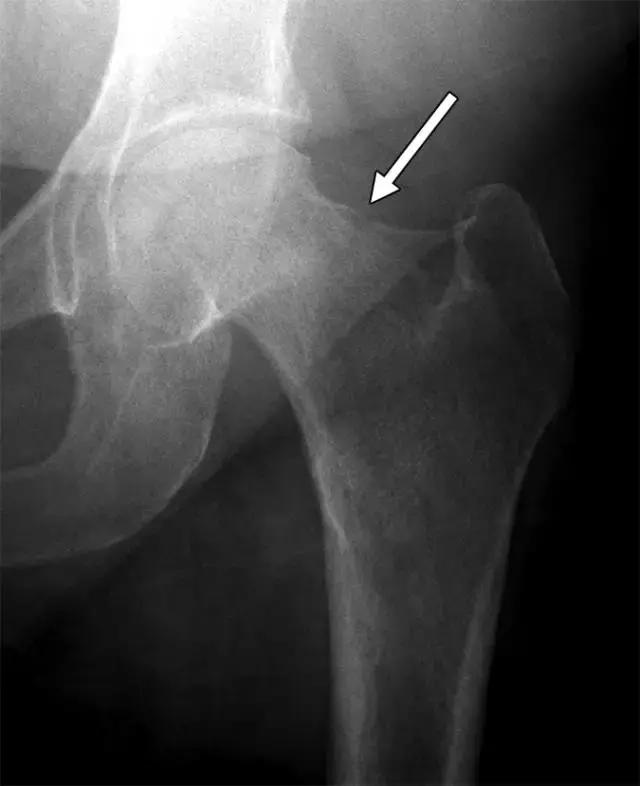

临床诊断可能是具有挑战性的,因为患者经常出现非特异性髋关节和腹股沟疼痛,因此成像通常在这些情况下起关键作用。 射线照片通常是不会发现的,特别是在有骨量减少的患者中,所以应该高度怀疑地看到沿股外侧的任何线性透视或硬化(图11)。 当临床怀疑近端股骨应激损伤时,应强烈考虑MRI,因为相关的骨髓水肿在脂肪抑制T2加权图像上显着,低信号强度骨折线也可能是明显的。

图11〜41岁女性患有糖尿病和外侧股骨颈应力骨折。 左髋前后X线片显示股骨颈侧向(拉伸)方面的局限性皮层破裂(箭头),MRI证实不完全骨折。